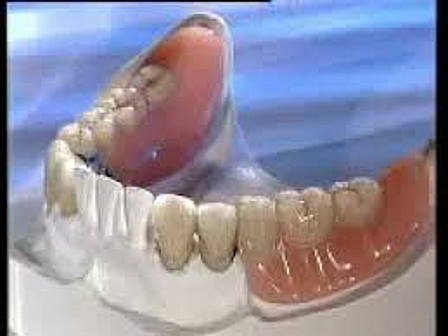

• FASE PROTESICA (COLOCACION DE PPR).

FASE PROTESICA (COLOCACION DE PPR).

Se confeccionan protésis parcial removible en ambas arcadas para sustituir los OD. 1.1, 1.2,1.6 y 2.1, 2.2, 2.4, 2.5, 2.6, 3.7, 4.5, 4.6, 4.7. se realizan las pruebas necesarias para lograr la adapatación, soporte y retención adecuada, con el fin de lograr la adecuada altura de la dimensión vertical. asi como la colocación de coronas libres de metal en OD. 1.3, 2.3, y 3.6. Quedando rehabiltado el paciente en su totalidad.